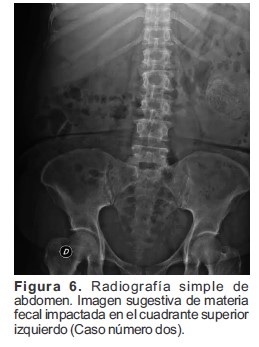

Se sugirió practicar colon por enema, el cual permitió visualizar, según la placa simple, una imagen sugestiva de materia fecal impactada, hacia el cuadrante superior izquierdo del abdomen (Figura 6). Se administró medio de contraste baritado, observándose abundante cantidad de imágenes diverticulares, las cuales dependían de todos los bordes del mesenterio y se distribuían desde el recto sigmoides hasta el ciego (Figura 7).

Figura 6. Radiografía simple de abdomen. Imagen sugestiva de materia fecal impactada en el cuadrante superior izquierdo (Caso número dos).

La imagen descrita en la radiografía simple se trató de un DCG que dependía del borde mesentérico del colon, a nivel del tercio distal del colon transverso de aproximadamente 7.5 cm x 6 cm de diámetro con un llenamiento parcial de medio de contraste (Figura 7). Debido a los hallazgos imagenológicos, se solicitó valoración por coloproctología, quienes consideraron que requería manejo quirúrgico y realizaron resección de colon transverso con anastomosis latero-lateral, con perforación contenida por epiplón.